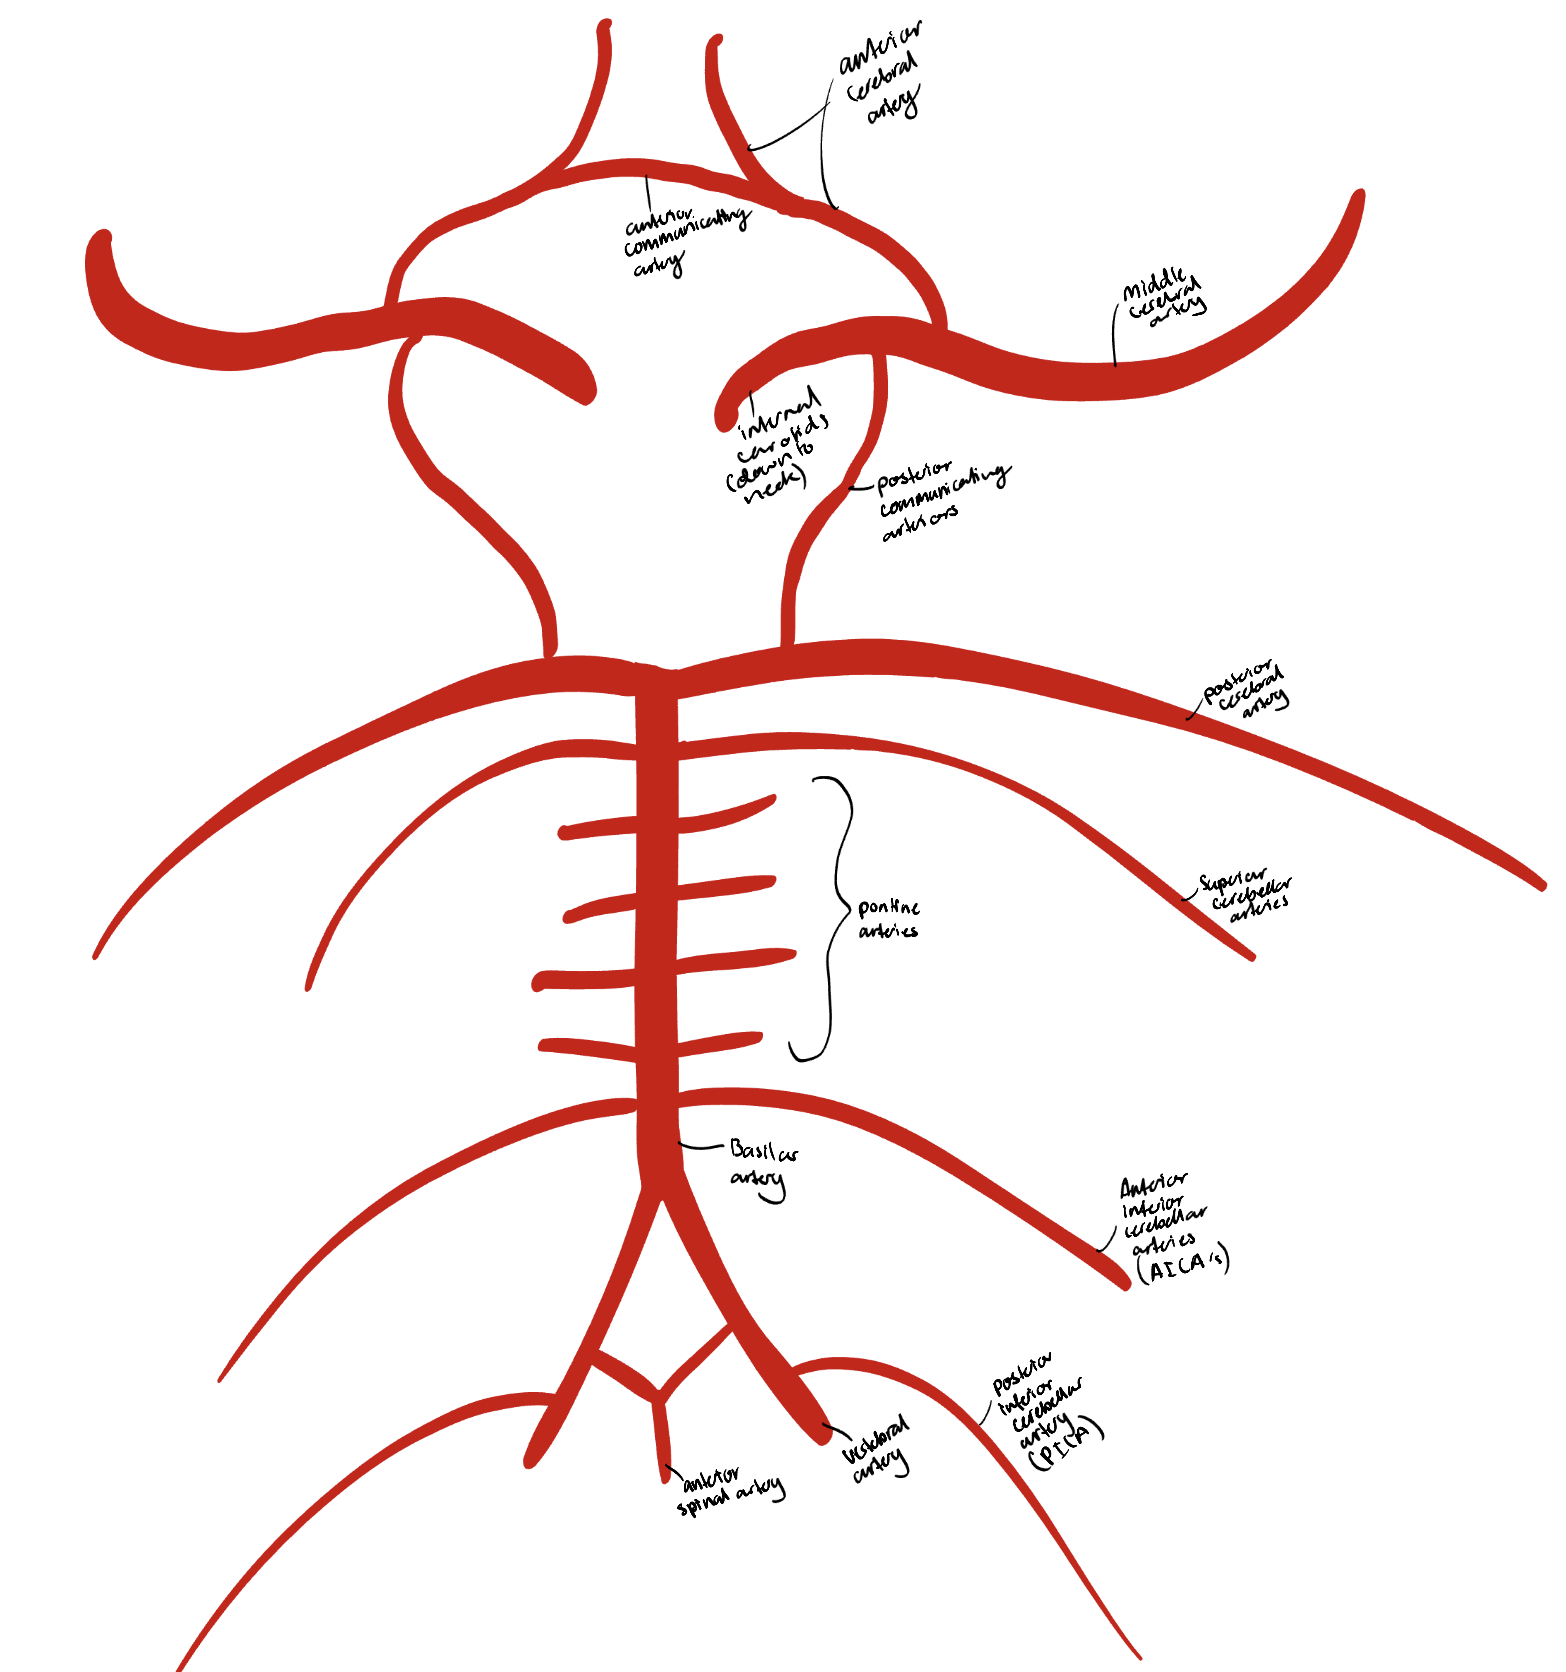

The arterial supply of the spinal cord + origins

Anterior spinal artery that originates inside the cranium from branches off the vertebral arteries.

Two posterior spinal arteries that originate in the cranium as branches off the vertebral arteries or the posterior inferior cerebellar arteries, and descend along the posterolateral sulci

The 8-10 segmental medullary arteries arise from the aorta.

The largest is the artery of Adamkiewicz in the lower thoracic region.

Segmental spinal arteries arise from vertebral and deep cervical arteries in the neck. The deep cervicals are branches from the subclavian artery that run up into the neck.

These branches go through the intervertebral foramina, and split into anterior and posterior radicular arteries.

The segmental arteries attach to the anterior and posterior spinal arteries.

Circle of Willis